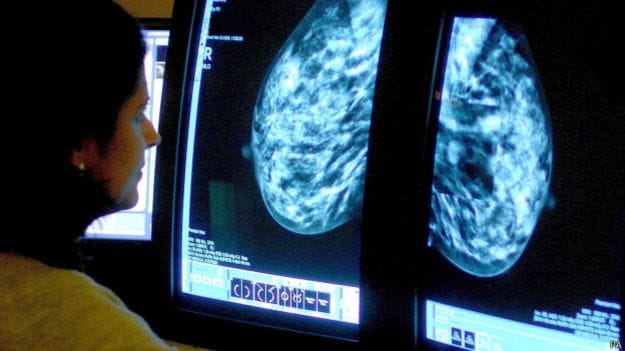

Exames para detectar câncer de mama estão sendo feitos por mulheres cegas na Alemanha. A ideia já existe há alguns anos, e uma pesquisa inédita sugere que pessoas cegas podem, de fato, detectar tumores mais cedo do que aquelas que enxergam.

Em um estudo ainda não publicado, realizado com a Universidade de Essen, mulheres cegas conseguiram detectar quase um terço a mais de nódulos que outros ginecologistas.

“Os médicos costumam encontrar tumores entre um centímetro e dois centímetros, enquanto os examinadores cegos encontraram nódulos com tamanhos entre 6 mm e 8 mm. Isso faz uma diferença real. Esse é o tempo que um tumor leva para se espalhar pelo corpo.”

Na Alemanha e no Reino Unido, mamografias regulares são oferecidas apenas a mulheres com 50 anos ou mais – mas, em ambos os países, o câncer de mama é a maior causa de morte de mulheres entre 40 e 55 ano, e na Alemanha, a idade das mulheres afetadas está caindo.